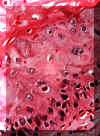

| Opuesta a la queratosis benigna, la displasia de la

mucosa ofrece anormalidades celulares significantes en el epitelio.

Esta microfotografía del epitelio escamoso normal,

que esencialmente es uniforme en un lado con una línea afilada de

demarcación entre este y el epitelio anormal en el otro. Incluso a

estos aumentos (resolución baja) uno puede descubrir la variación en

el tamaño, forma y pigmentación de las células. No hay ninguna invasión

del epitelio hacia el tejido conjuntivo. Esta es la característica que

distingue a la displasia de la mucosa del carcinoma espinocelular. |